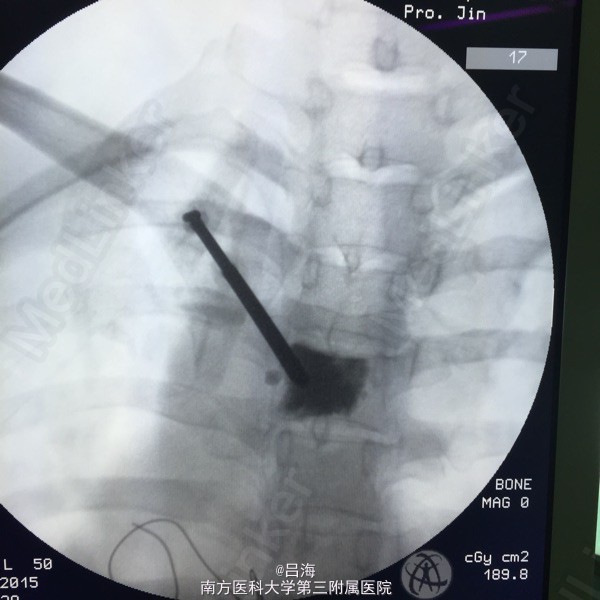

胸4棘突扣痛,并向左侧肋部放射。 胸椎MRI提示:胸4椎体血管瘤,侵袭椎体约80%。

胸4椎体血管瘤 局麻下行经皮活检,椎体成形术

患者背痛并左肋部症状明显缓解,术后第二天出院。 椎体血管瘤多数可不手术,但如患者椎体破坏严重,症状进行性加重,这可考虑手术治疗